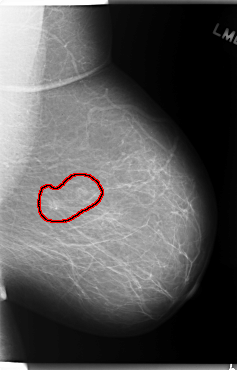

FILE: C_0132_1.LEFT_MLO.OVERLAY

TOTAL_ABNORMALITIES 1

ABNORMALITY 1

LESION_TYPE CALCIFICATION TYPE PLEOMORPHIC DISTRIBUTION CLUSTERED

LESION_TYPE MASS SHAPE OVAL MARGINS ILL_DEFINED

ASSESSMENT 4

SUBTLETY 4

PATHOLOGY MALIGNANT

TOTAL_OUTLINES 1

BOUNDARY